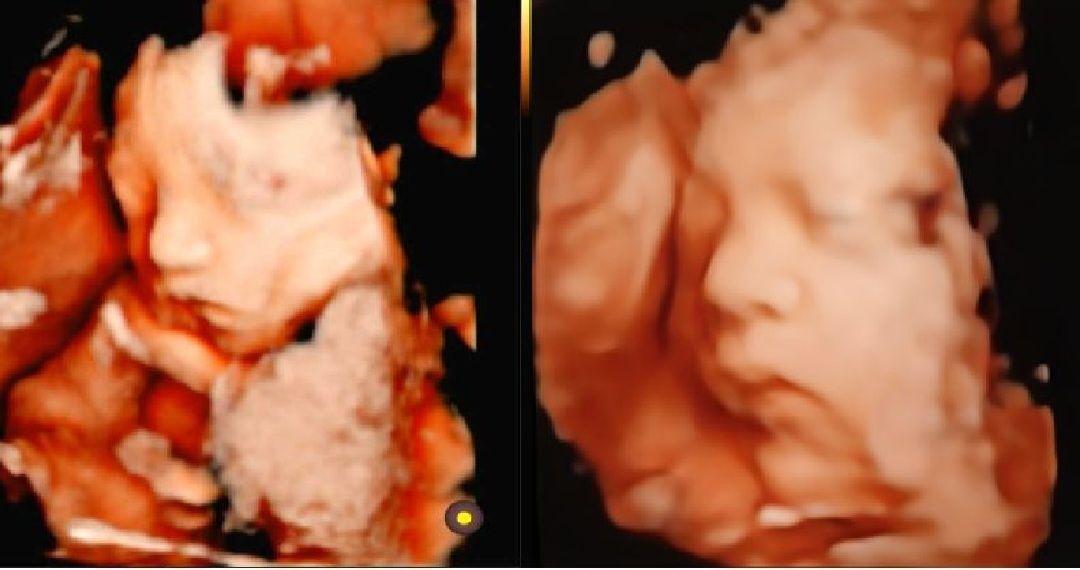

28주차 입체초음파🩵

내내 뒤돌아있다구 얼굴을 안보여주더니 드디어 입체초음파 성공했네요^^ 쌤이 콧대도높고 잘생겼다 하시는데 우린 안닮은듯요ㅎㅎ 괜히 기분이가 좋트라구요~~ 이정도면 베이비페이스 성공할까요? 완전정면은 아니라서...